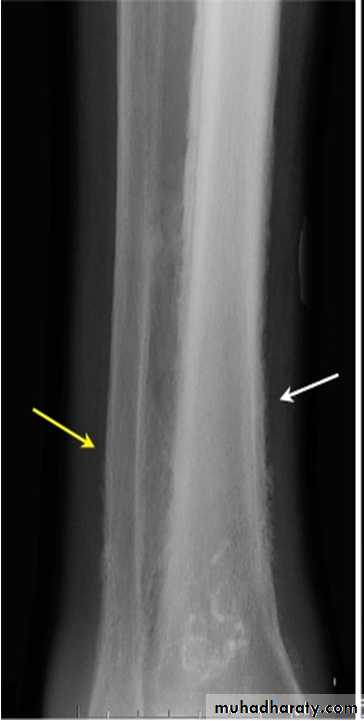

Hypertrophic pulmonary osteoarthropathy (HPOA). This is a painful periostitis of the distal tibia, fibula, radius and ulna, with local tenderness. X-rays reveal subperiosteal new bone formation. While most frequently associated with bronchial carcinoma, HPOA can occur with other tumours.